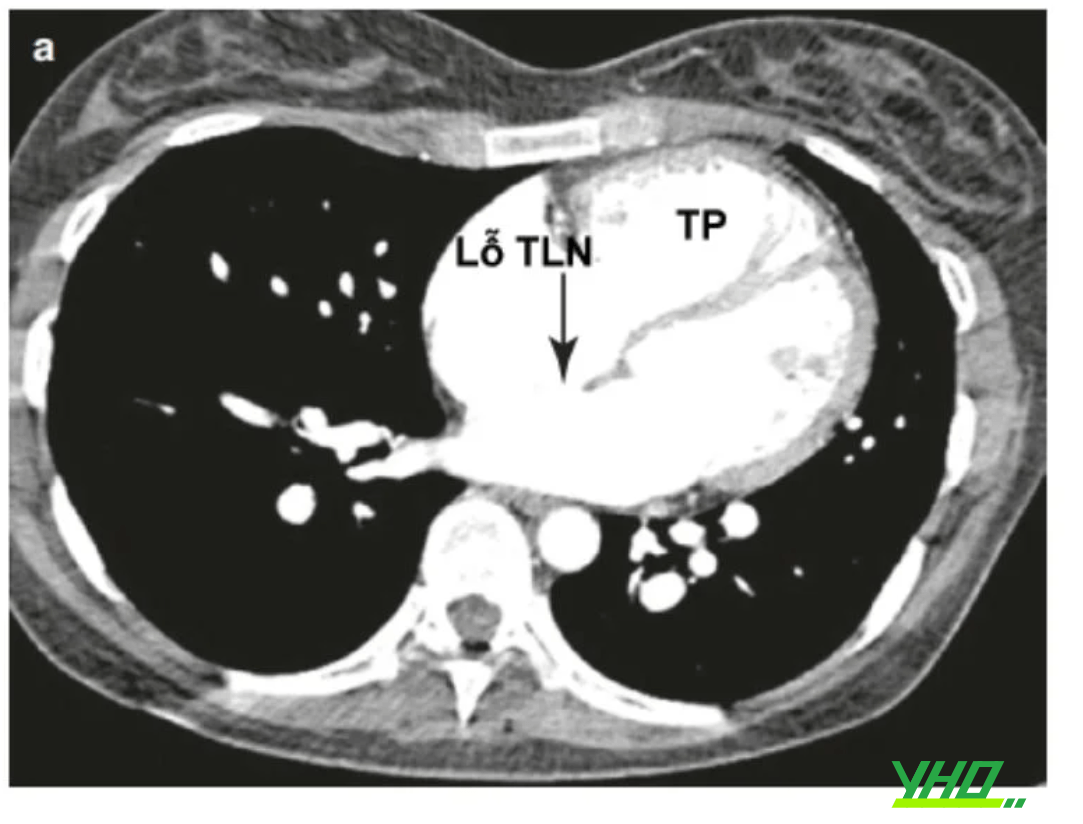

Chụp cắt lớp vi tính đa dãy tim (MSCT) có thể cho các thông tin như nhìn thấy trực tiếp khuyết vách, đánh giá được giải phẫu quanh lỗ thông, đo được kích thước các gờ xung quanh, xác định được bất thường đổ về tĩnh mạch phổi. Tuy nhiên, tăng nguy cơ phơi nhiễm phóng xạ đặc biệt ở bệnh nhân trẻ.

Chú thích: TLN: Thông liên nhĩ; TP: Thất phải.